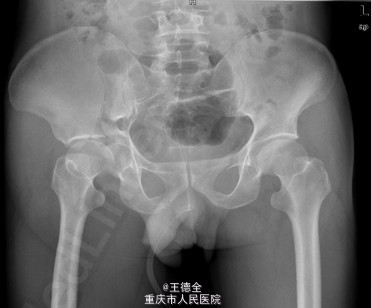

患者男性,51岁,因“高坠伤致左腰部及右髋部疼痛伴活动障碍3天”入院。

查体:急性痛苦面容,神志清楚,平车送入病房,右髋部软组织稍肿胀,局部皮肤完整,未见明显皮疹,挫擦伤及出血点.右股骨髁上骨牵引在位,左腰椎伴明显压痛,骨盆挤压实验阳性,可扪及骨擦音,骨擦感.双下肢感觉,活动,血循良好,足背动脉搏动好;右踝关节主动活动受限,被动活动正常。右侧各足趾背伸、跖屈活动正常,其余各关节活动正常。骨盆X线片示:右侧髂骨、髋臼、双侧耻骨上支、右侧耻骨下支多发骨折,左侧髂骨翼骨折,骨盆出入口右侧份形态失常。辅查影像学资料见下图。

初步诊断:右髋臼粉碎性骨折(Judet X 型) ,诊疗计划:完善双下肢静脉彩超等检查;给予预防深静脉血栓、骨牵引治疗;给予止痛等对症支持治疗;密切观察病情变化,根据病情及时处理。